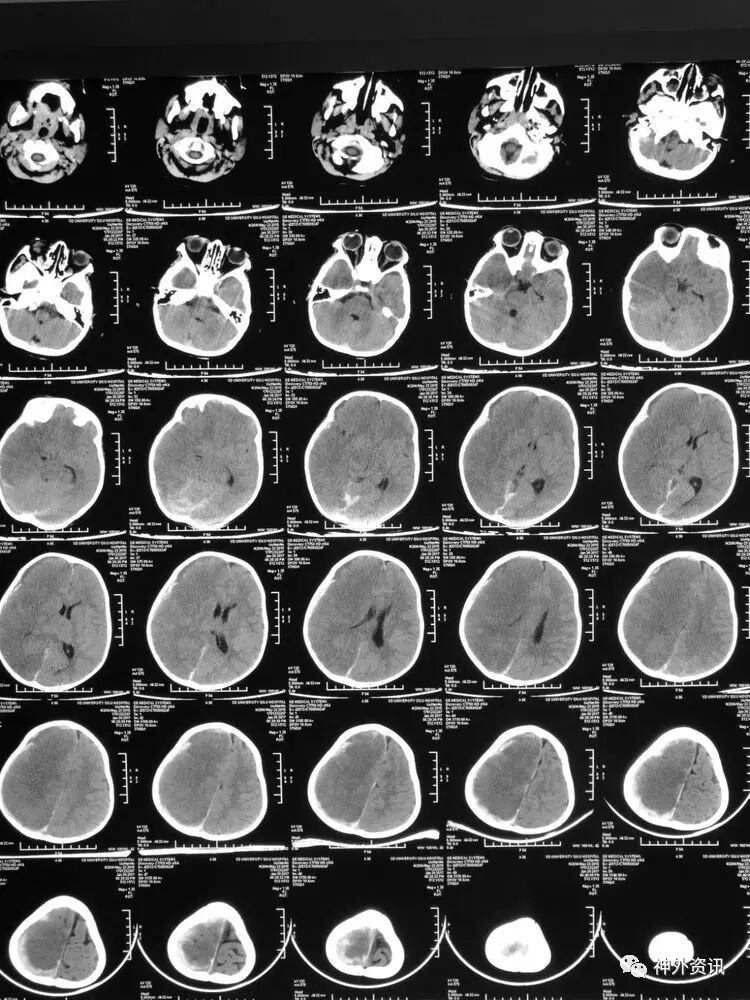

2017.2.4:术后5天复查颅脑CT,结果示中线居中,左侧半球及环池显示清晰,右侧半球脑沟显示欠清晰,脑组织低密度较前有所好转,继续同前治疗。已加用预消化肠内营养液及促进胃肠动力药物。

2017.2.6:术后7天,复查颅脑CT示情况较前进一步好转,逐步撤掉冰毯,缓慢自然复温。

2017.2.8:术后9天,复查颅脑及胸部CT,结果显示双侧脑沟脑回及环池显示清晰。颅压控制,拔除引流管探头,头部敷料稍加压包扎,此时已更替力月西为丙泊酚,停用呼吸机。